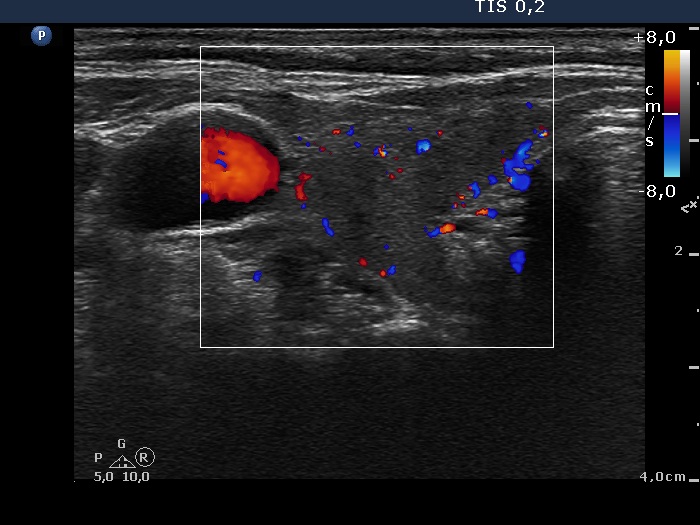

Graves' disease - case 18

Follow-up investigation 6 weeks after the first visit (ultrasonographic picture 3)

Right lobe, transverse scan, color Doppler method. The vascularization is decreased.